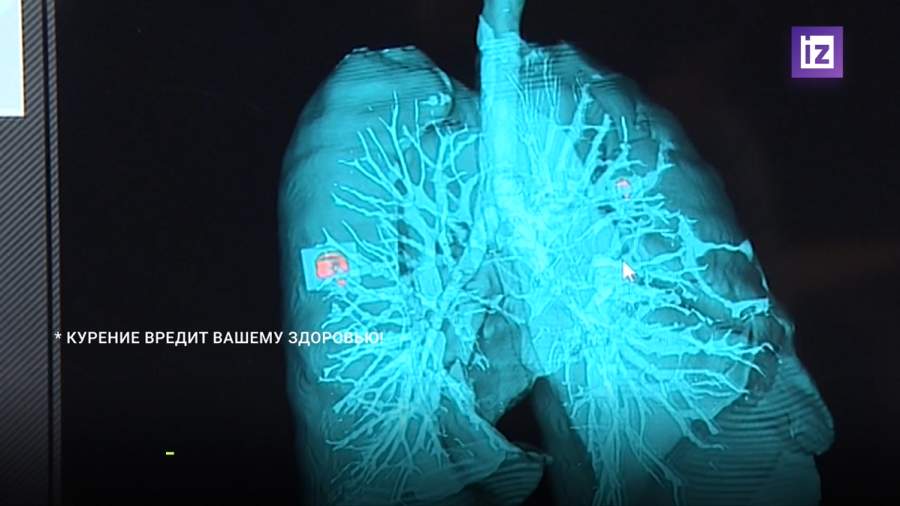

Как лечить evali

Как лечить evali 106 фото